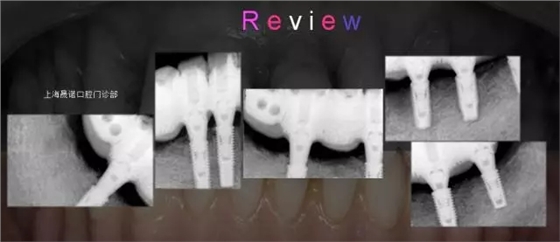

男46歲 患者主訴: 下頜牙缺損伴疼痛,無法滿足日常飲食需求,要求修復(fù)。 診斷: 牙列缺損,中晚期牙周炎。 治療方案: (1)確定終修復(fù):種植體支持的全牙弓一體式 CAD/CAM全鈦烤塑復(fù)合橋。 (2)種植外科前面弓轉(zhuǎn)移,確定咬合關(guān)系。 (3)根據(jù)R2GATE制作標(biāo)準(zhǔn)拍攝CBCT。 (4)R2GATE種植方案確定及生成。 (5) 種植外科:結(jié)合臨床條件及R2GATE植入EZPlus,鎖定八角基臺。 (6)即刻負(fù)重:被動性印模,當(dāng)日完成種植體支持的螺絲固位臨時橋修復(fù)體。 (7)終修復(fù):依據(jù)患者臨時橋修復(fù)體的佩戴情況,評估及完成終修復(fù)。終修復(fù)為全牙弓一體式CAD/CAM全鈦烤塑復(fù)合橋。 (8)隨訪和專業(yè)口腔衛(wèi)生維護(hù):第一次3個月;第二次半年~一年。放射對照性檢查為每年一次。 術(shù)前口內(nèi)檢查 術(shù)前影像檢查分析 種植位點設(shè)計 種植位點評估 R2GATE導(dǎo)航系統(tǒng)設(shè)計種植體分別為 右下4:EZplus 4*11.5mm; 右下6:EZPlus 4.5*10mm; 左下5:EZPlus 4*10mm; 左下6:EZPlus 4.5*10mm; 左下7:EZPlus 4.5*7mm. R2種植導(dǎo)板 收到R2GATE導(dǎo)板及手術(shù)報表,導(dǎo)板外科工具盒。 治療步驟 第二周9:30-11:30:摘除R2GATE,33、43即拔即種。拔除34、44、45、46;口內(nèi)就位R2GATE,44、46、35、36、37不翻瓣導(dǎo)航下完成全程備洞。 35(EZPlus 4.0*10mm) 36(EZPlus 4.5*10mm) 37(EZPlus 4*8.5mm) 33、43(EZPlus 4.0*13mm) 44(EZPlus 4.0*11.5mm) 46(EZPlus 4.5*10mm) 植入扭力都大于50Ncm,分別35N鎖定八角基臺,并用手?jǐn)Q緊八角愈合帽,將骨引導(dǎo)材料(Bio-Oss,Geistlich)植入骨缺損區(qū)。